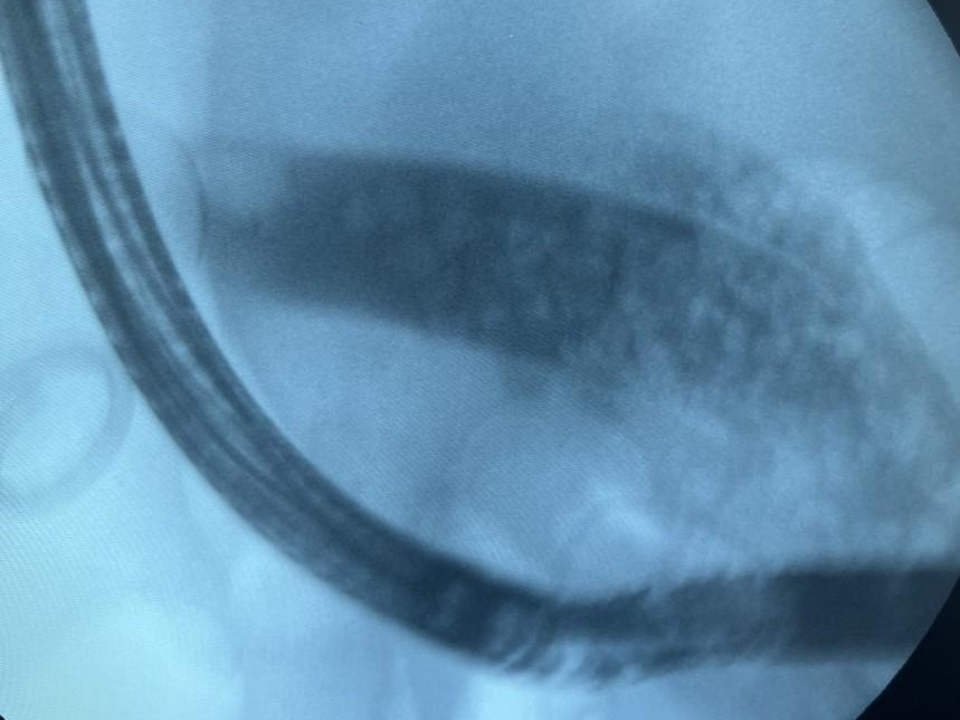

Для уточнения диагноза была выполнена МР-холангиография — высокоточный метод магнитно-резонансной визуализации желчных протоков. Это исследование подтвердило предыдущие данные: специалисты выявили увеличенный желчный пузырь с множественными мелкими камнями внутри, при этом главный проток оказался полностью забит конкрементами. Для лечения таких патологических состояний в современной медицине применяются как традиционные хирургические, так и малотравматичные эндоскопические методы, главные преимущества которых заключаются в сокращенном времени восстановления пациента.

Завотделением эндоскопии Агарон Айвазян подробно описал ход вмешательства. Он сообщил, что врачи выполнили рассечение большого дуоденального соска, сфинктеротомию, затем с помощью специального баллонного инструмента расширили устье желчного протока до необходимых размеров.

После проведения этих этапов желчь и камни начали активно поступать в просвет кишки. Крупные камни были перемещены в кишечник специальной корзиной, откуда в дальнейшем они вышли естественным путем. В общей сложность из организма женщины было удалено более 50 камней. При контрольном осмотре протоков камней обнаружено не было.